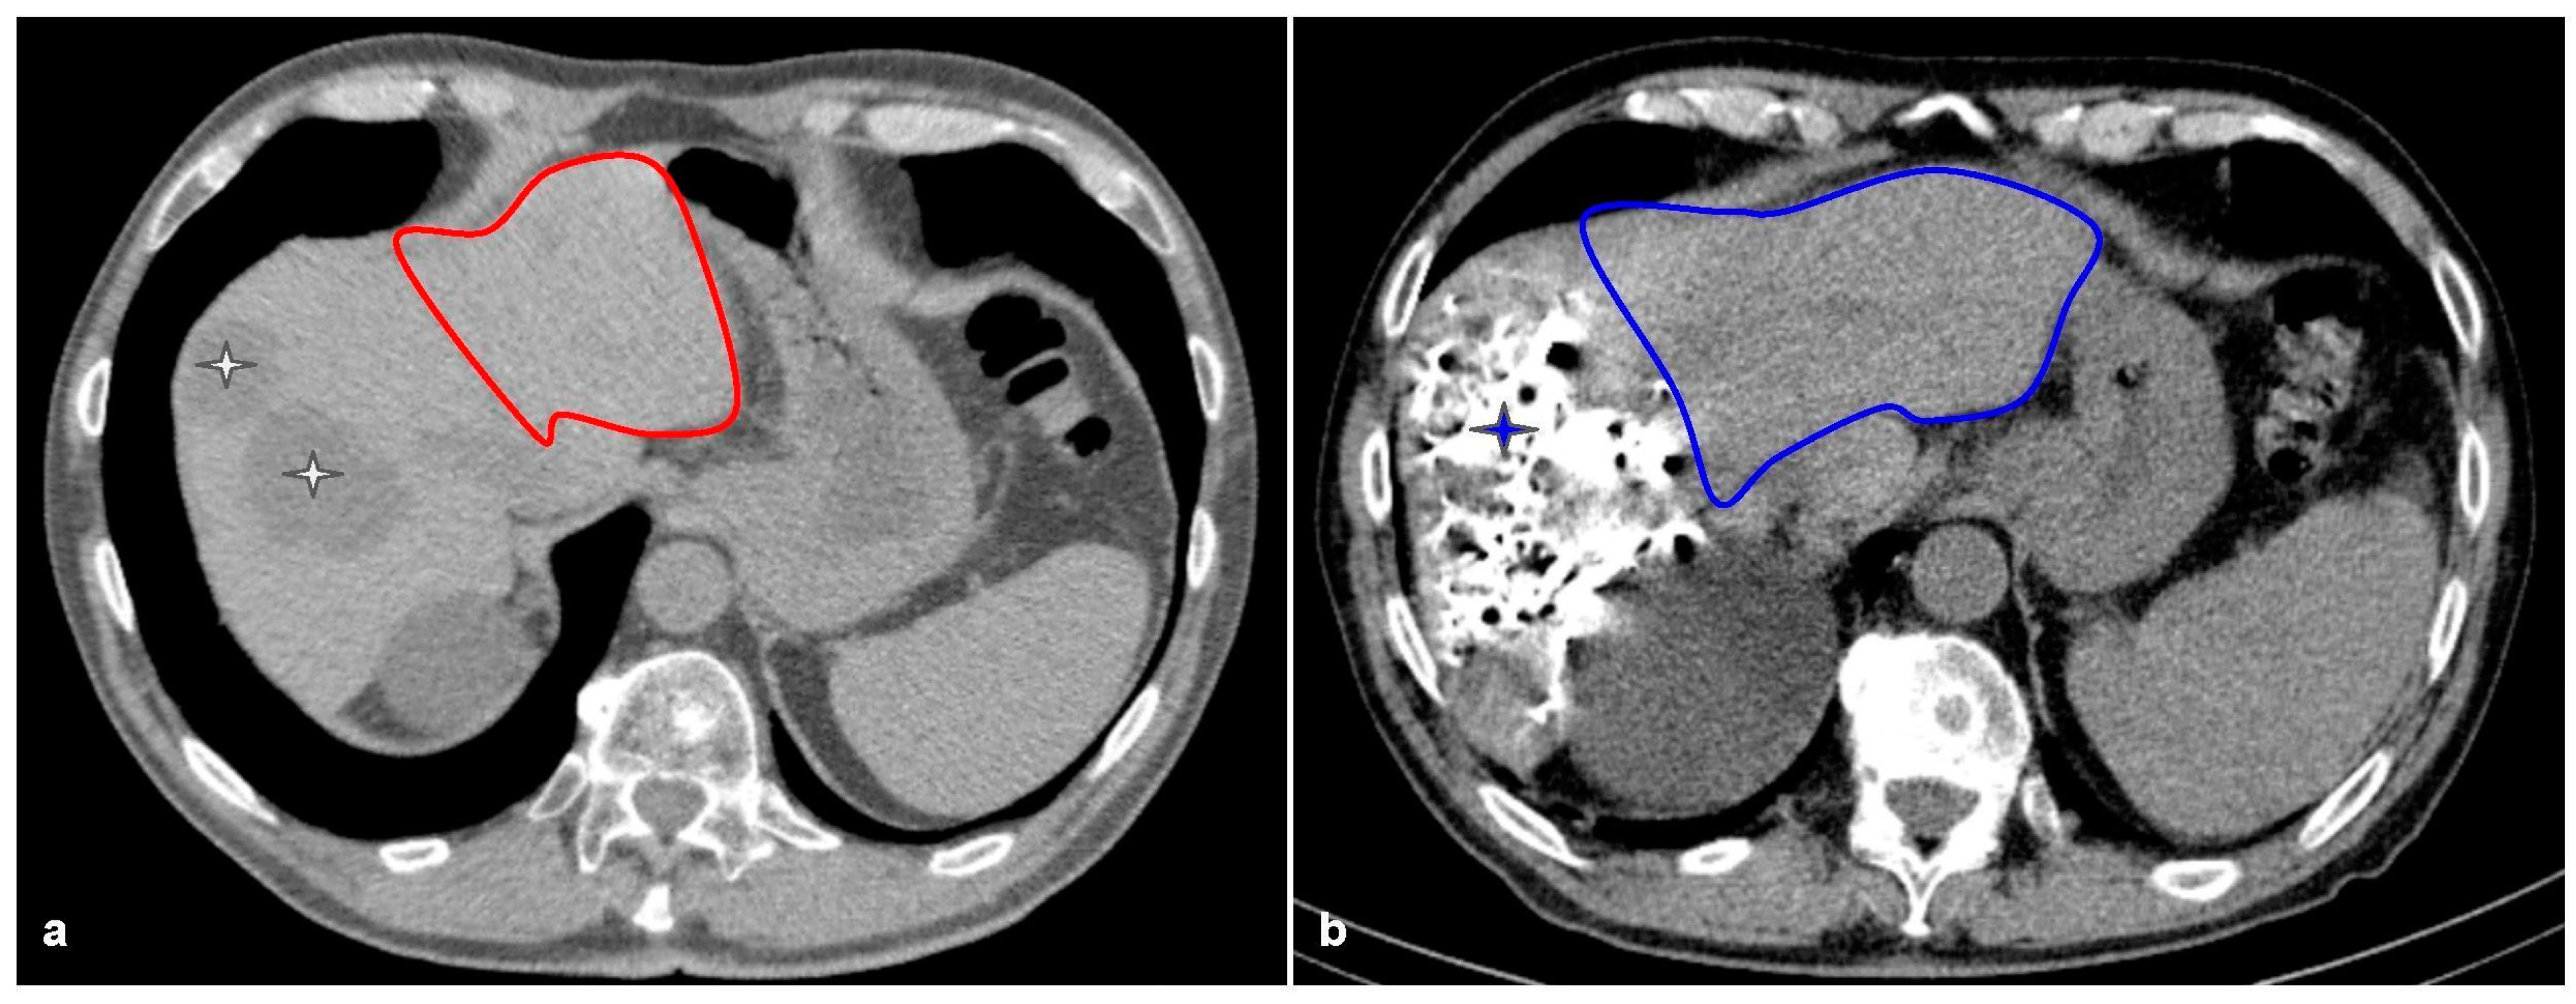

2. Calculating the Future Liver Remnant and Making It Grow: From Volumetrics to Portal Vein Embolization